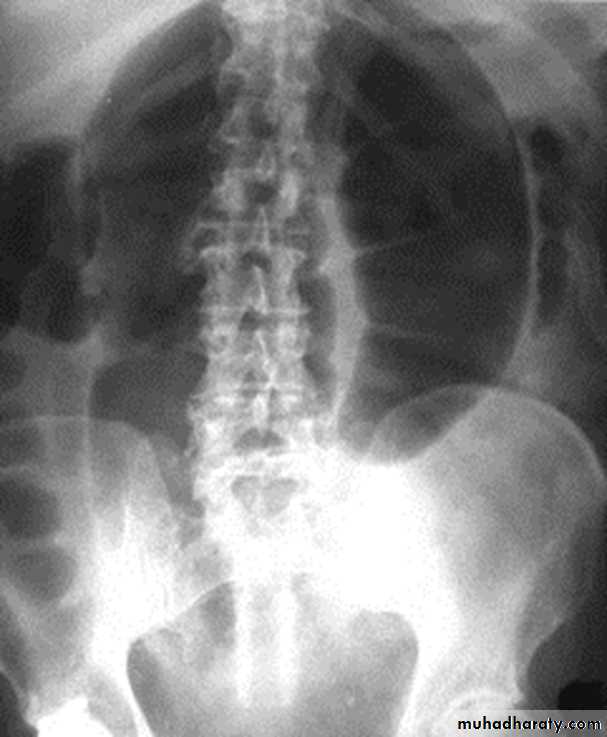

Slide 61- what does the Xray shows? What is the diagnosis?2- Mention the cardinal clinical picture of this condition.